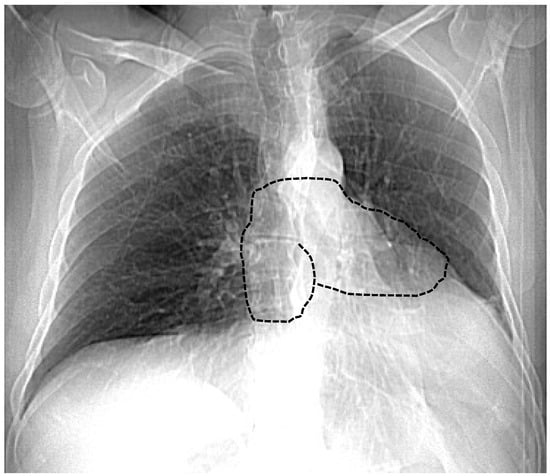

7.1. Chest X-ray

| Chest X-ray | Leftward heart displacement (Snoopy sign) Prominent main pulmonary artery Radiolucency between the heart and diaphragm | Availability Low cost Bed-side evaluation | Low sensibility Low specificity |